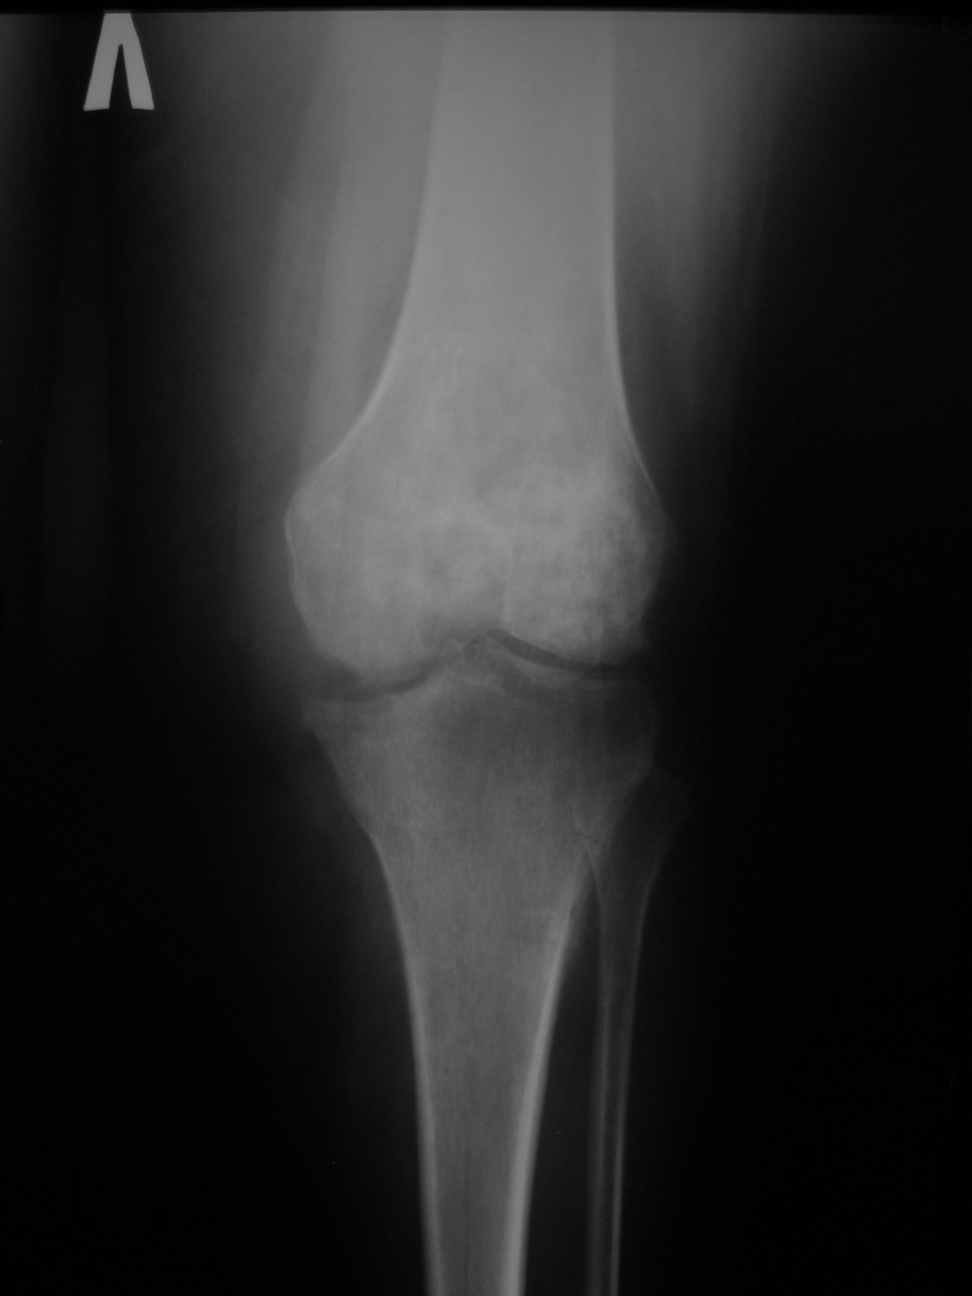

Уважаемые коллеги, просим совета. В госпиталь переведена женщина, врач, 1970 года рождения, 110 кг. 26.10.2009 г. в левый коленный сустав однократно введен Дипроспан по поводу деформирующего артроза. 02.11.2009 развился гнойный гонит. Полость сустава дренирована, проточно-промывное дренирование, наложен спице-стержневой КДА. Развился остеомиелит бедра и голени. Демонтирован КДА. По стихании гнойного процесса и заживлении ран начато реабилитационное лечение. При поступлении к нам: Ходит на костылях с дозированной нагрузкой на левую ногу. На передней поверхности бедра и голени втянутые рубцы от спиц и стержней без признаков воспаления. Левый коленный сустав деформирован, вальгусная установка, разгибание 175 градусов, сгибание 120, движения болезненны. Надколенник фиксирован. При вальгусной нагрузке резкая болезненность. Осевая нагрузка безболезненна. При ходьбе - чувство нестабильности и боль по наружной поверхности сустава. Трофических и неврологических расстройств на конечности нет. Хочется услышать мнение о тактике лечения. По нашему мнению, возможности эндопротезирования на настоящий момент, учитывая наличие остеомиелита, нет. Показано ли артродезирование? Как вариант рассматривается артродез длинным гвоздем с цементной муфтой и антибиотиками. Если все же готовить больную для протезирования в отдаленном периоде, целесообразно ли выполнить артроскопический артролиз в ближайшее время для восстановления амплитуды движений в коленном суставе? Можно ли ожидать спонтанного анкилоза при опорной нагрузке без операций? С уважением, Александр Мешков.ФГУ "574 ВКГ МВО" МО РФ г. Москва.